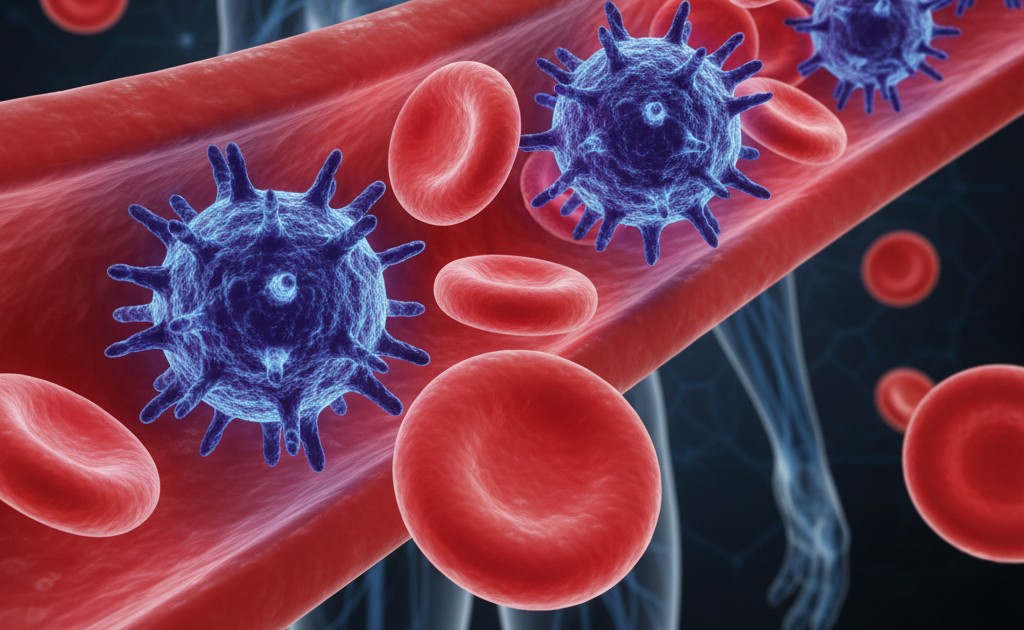

Blood Cancer For the Symptoms, Stages, and Treatment

Hematologic cancer, it can involves changes for the production and functions of blood cells, primarily…